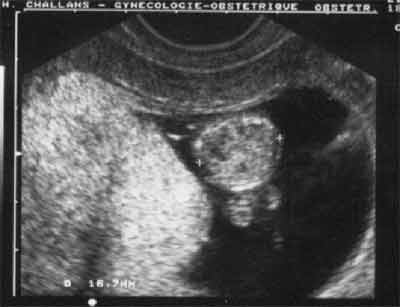

Coupe transversale